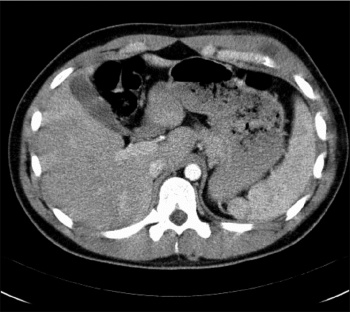

Figure 1: Ultrasound of anterior chest wall – hypoechoic complex fluid collection in the left chest wall

Figure 1: Ultrasound of anterior chest wall – hypoechoic complex fluid collection in the left chest wall(click to enlarge)

On investigations inflammatory markers were raised. Ultrasound of the affected side of the chest wall showed a 4cm soft tissue lesion with heterogeneous echotexture and decreased Doppler signal, suggesting further evaluation with CT (Figure 1).